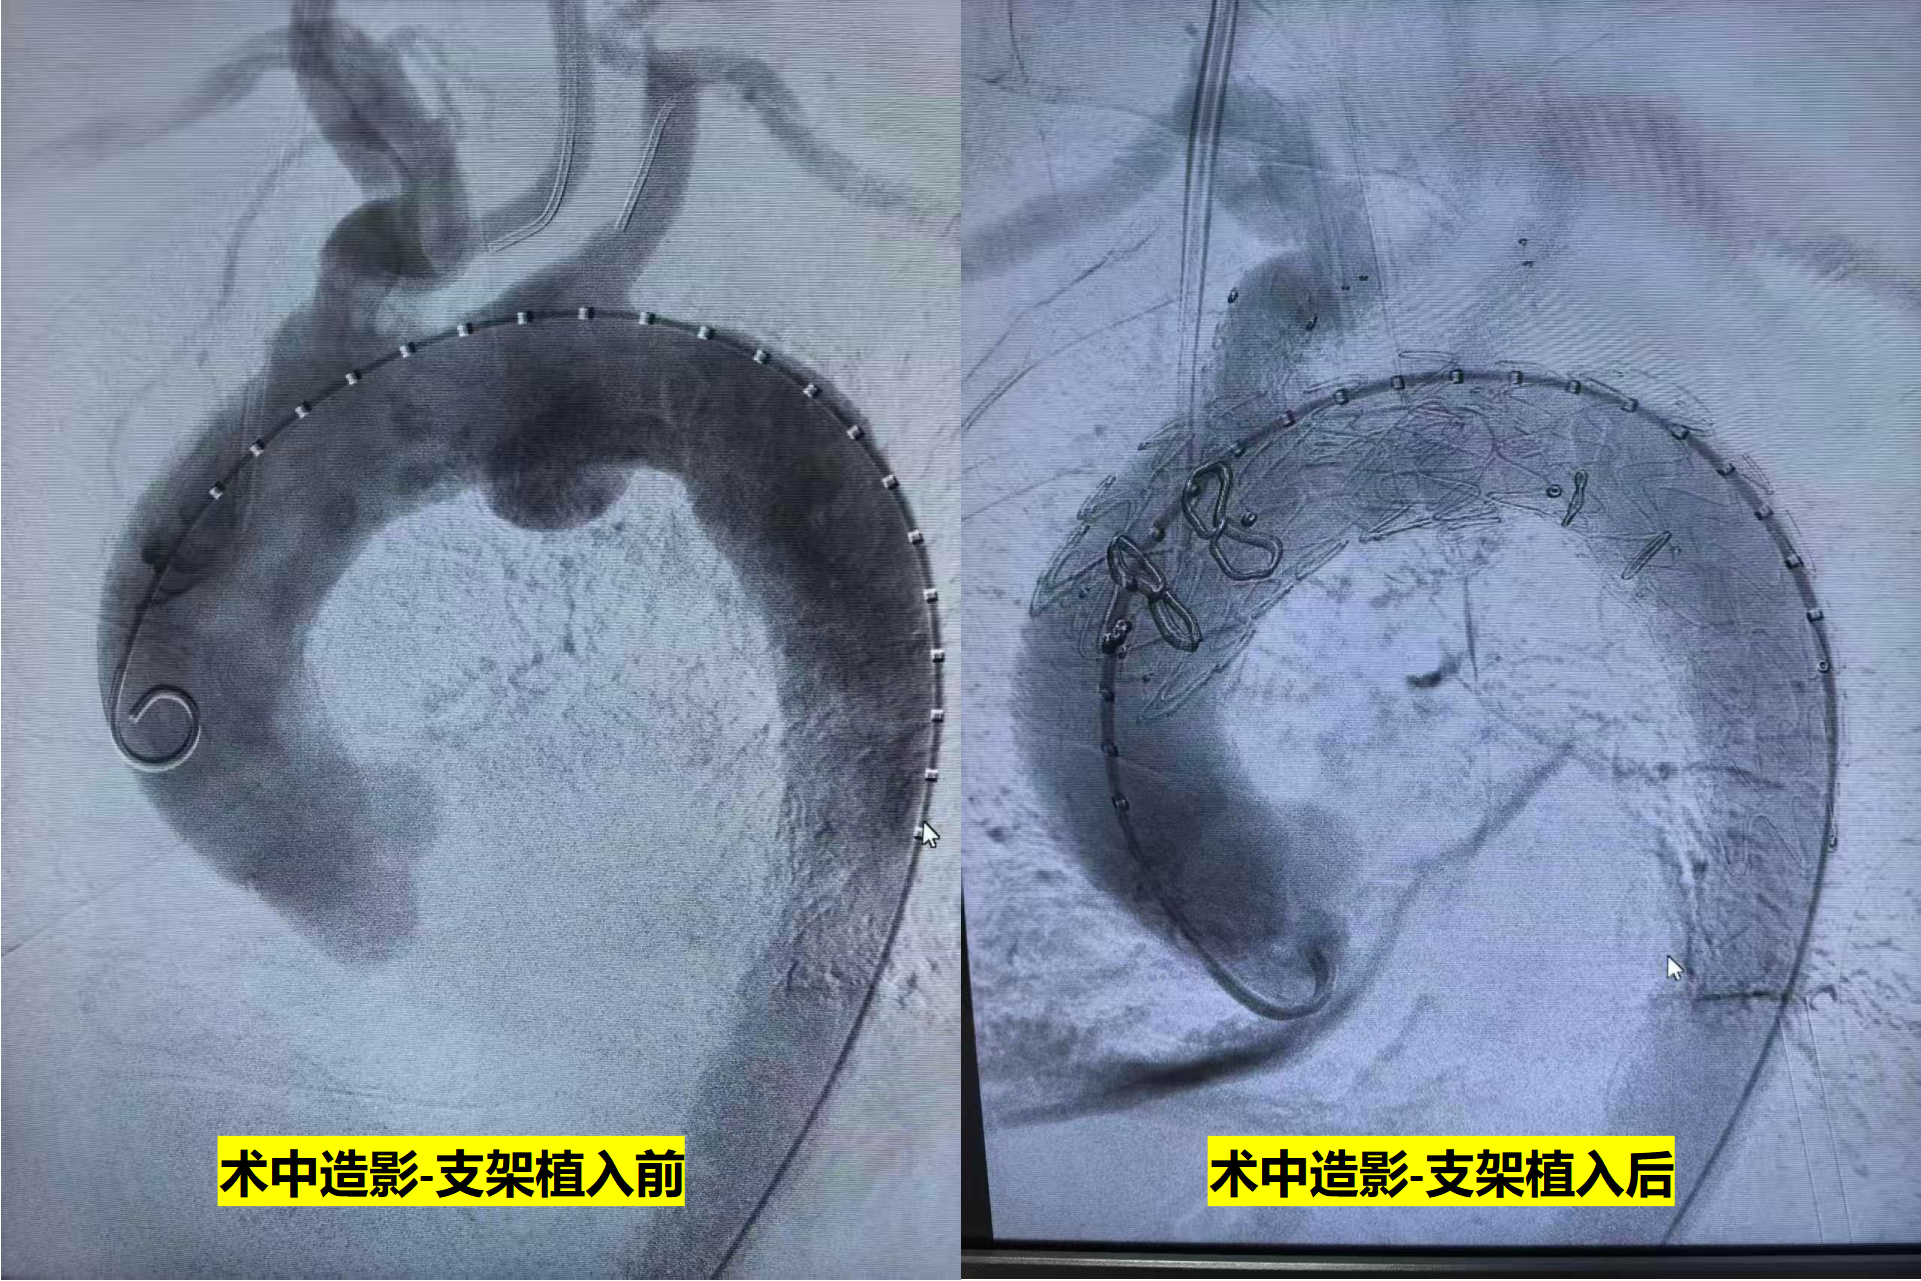

专家们通过老人大腿根部、手臂和脖子上的几个“小口子”建立通道,把一款特制的覆膜支架系统精准送到病变部位。支架展开后,相当于在血管内部搭建了一条“人工血管”,让血液改走新通道,不再冲击动脉瘤,从根源上消除了破裂风险。“简单说,就是从血管里面把‘炸弹’包起来。”舒畅教授打了个比方。这项新技术,不用开胸、不使心脏停跳,整个手术对心肺的干扰降到了最低。

据悉,该技术全球已成功应用超100例,为更多高危血管病患者带来新希望。目前,王大爷已顺利出院,恢复得比预期快得多。复查显示,其动脉瘤被完全隔绝,血管通畅。